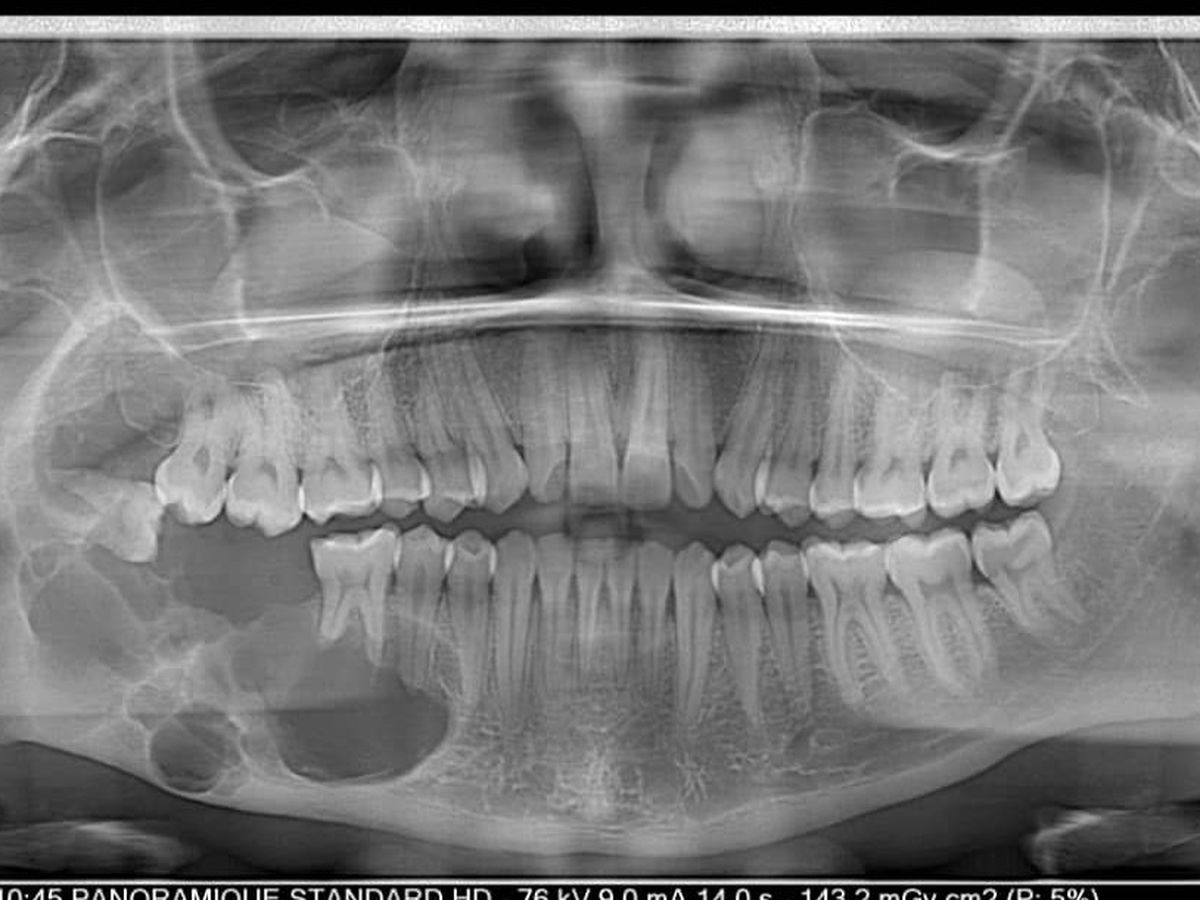

Eines Tages besuchte uns während unseres Einsatzes in Togo ein junger Mann, Kokou Amegavi. Bei der Untersuchung stellten wir einen großen Tumor im Unterkiefer fest. In der Röntgenaufnahme zeigte sich uns ein Bild, das uns erschreckte. Bitte schauen Sie sich das Röntgenbild an. Selbst für Sie, die sie vielleicht nicht vom Fach sind, ist die knöcherne Zerstörung deutlich zu sehen.

Dieser Tumor ist nicht nur eine körperliche Last, die Kokou täglich trägt, sondern auch eine stille Bedrohung und damit eine tickende Zeitbombe. Die Zeit drängt, denn ohne Behandlung droht der Verlust seines rechten Unterkiefers – und damit ein Stück seiner Menschlichkeit.